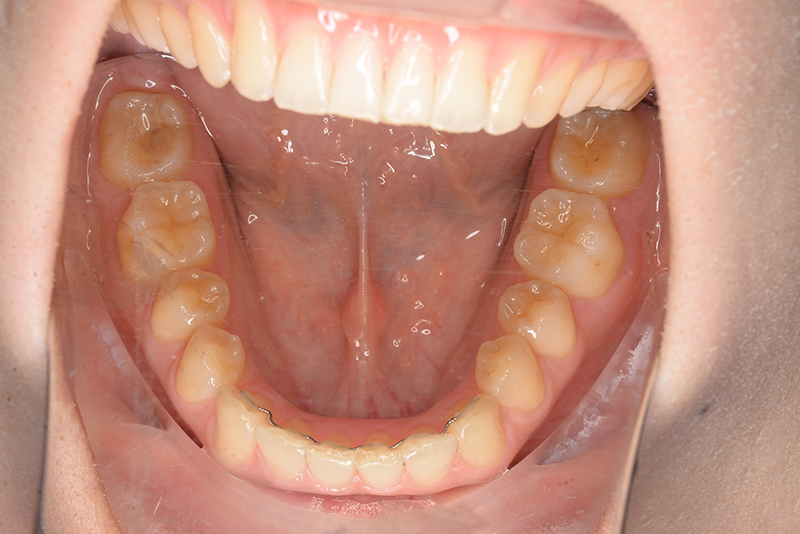

初診時

FP・IOP

口腔内所見 大臼歯、犬歯関係はⅡ級で、上顎中切歯は舌側傾斜しており、over jet1.5mm,over bite 6.0mmいわゆるⅡ級2類であった。